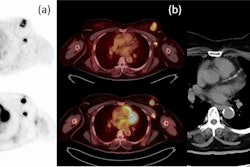

A 49-year-old patient with primary clinical stage III melanoma underwent F-18 FDG-PET. The primary tumor Breslow thickness was 6.5 mm. On initial F-18 FDG-PET images, this patient had a high SUVmax (52), resulting in limited survival with the occurrence of brain metastasis in the first year of follow-up (horizontal arrow). Notably, during the course of the treatment, the patient underwent surgical removal of the primary tumor as well as lymph node dissection, followed by neoadjuvant radiotherapy and immunotherapy. Image courtesy of Cancers.